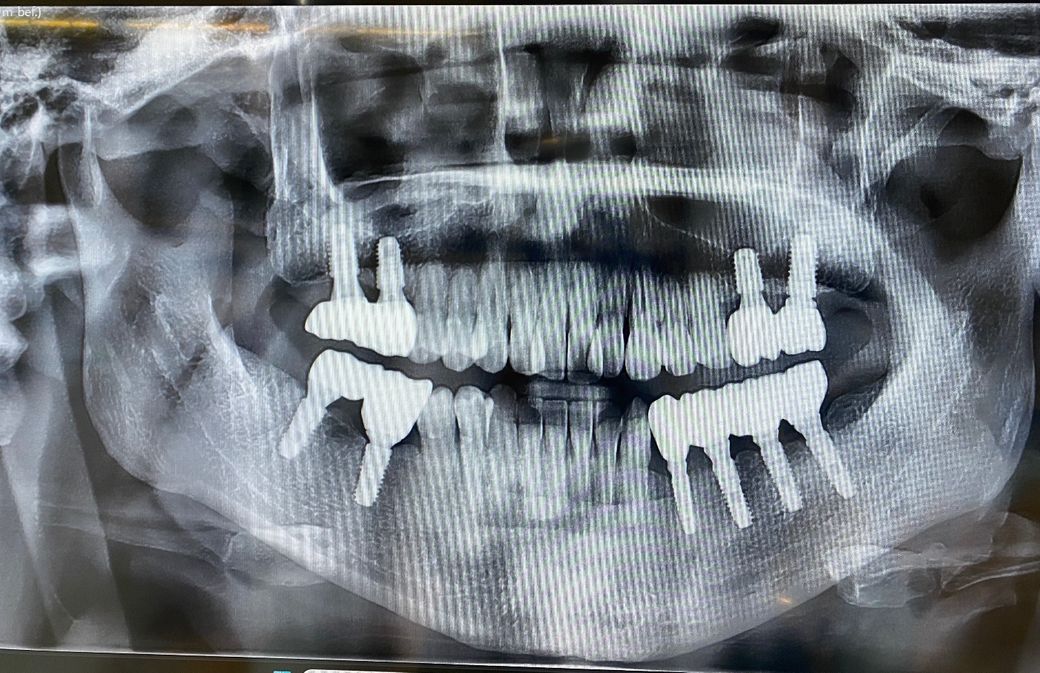

2016년에 식립하여 2017년 7월에 마무리해서 지금까지 사용하고 있습니다.

9년정도 사용하고있는데 코로나와 일적인 관계로 2025년에 치과를 방문하여 x-ray사진을 찍었습니다. 치과에 정기적으로 방문하지 않아서 스케일링도 올해들어 했습니다. ㅠ

전체적으로 잇몸뼈 손실이 있는지 그리고 갈 수로 잇몸이 내려앉아 사진처럼 지대주가 보이고, 잇몸과 치아사이에 블랙트라이앵글도 더 크게 생겼습니다. 지대주가.노출되면 더 주위염에 노출될 위험이 큰지? 아니면 청소가.더 잘되서 더 유리한지? ㅜ 알려주세요. ㅜ

(아래 사진은 2017년 7월 사진)

(아래사진은 2025년4월 사진)

사진에 보이는 정도는 큰 문제가 잇는건 아닙니다. 관리를 잘하시면 상관없으니 정기적으로 치과를 다니시면서 관리를 받으시면될것같습니다.

사진으로 봤을 경우에 임플란트를 둘러 싸고 있는 치조골의 양은 잘 유지가 되고 있는것으로 보입니다.

잇몸의 염증이 없다면 붓기가 가라않으면서 블랙트라이 앵글이 생기는 경우도 있습니다.

임플란트 주변을 꼼꼼이 양치질하고 치간칫솔을 사용해 보세요.

워터픽을 사용하면 임플란트 주위를 더 깨끗하게 관리할수 있습니다.